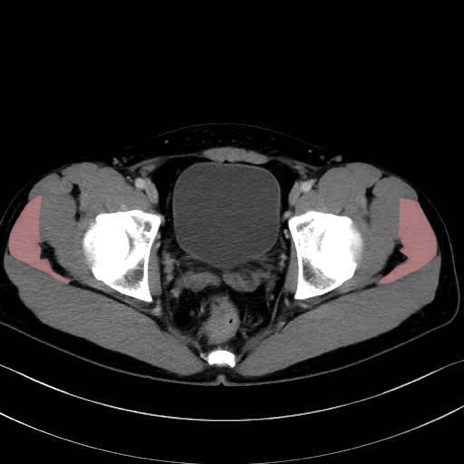

3. 殿部の筋肉(表層・中層・深層)

大殿筋 (Gluteus maximus)

中殿筋 (Gluteus medius)

小殿筋 (Gluteus minimus)

大腿筋膜張筋 (Tensor fasciae latae)